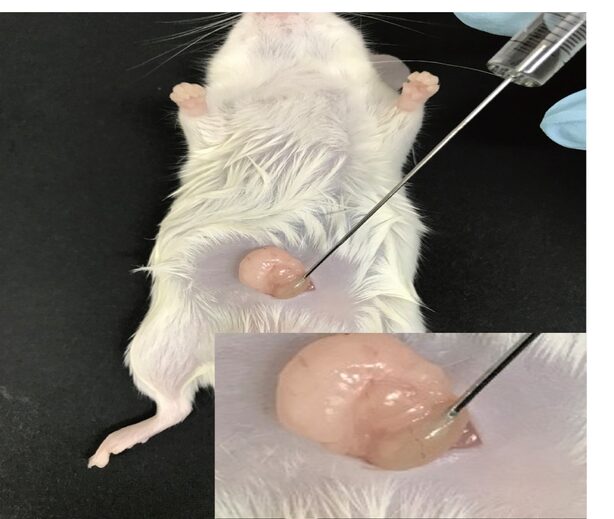

- Cell transplant from blood as IP, sub-kidney and muscle capsule

- Tracking of transplanted cells